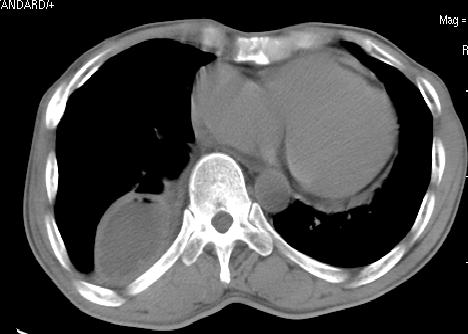

心包积液(少量).